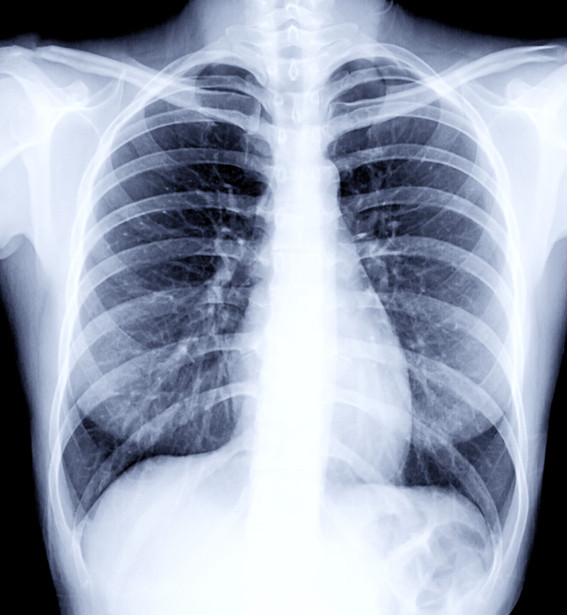

वैदेशिक रोजगारीको लागि अनिवार्य हुने स्वास्थ्य परीक्षणमा Chest X-ray गरिन्छ। यसमा फोक्सो (lungs) को अवस्था हेर्ने गरिन्छ।

छातीमा दाग भन्नाले प्रायः फोक्सोमा पुरानो रोग, संक्रमण वा चोटपटकपछि बाँकी रहेको ‘scar’ (घाउको निशान) लाई जनाउँछ। यो दाग प्रायः सामान्यतया मानिसलाई थाहा नहुने गरी हुन्छ र X-ray गर्दा मात्र देखिन्छ।

• रोग निको भए पनि X-ray मा सानो वा ठूलो दाग जीवनभर देखिन सक्छ।

• फोक्सोमा भएको पुरानो निमोनिया, pleurisy आदि निको भएपछि पनि दाग देखिन्छ।